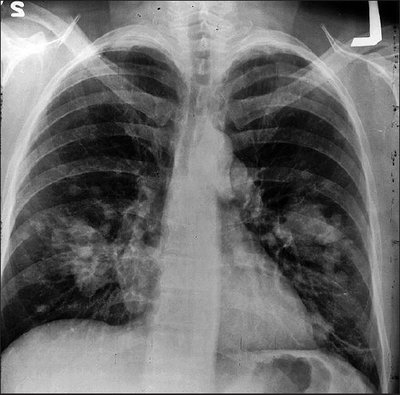

Question 13

Question

Revalida - 2012 Um paciente do sexo masculino, 55 anos de idade, tabagista 60 maços/ano, com tosse crônica há mais de 10 anos, relata que há cerca de três meses observou a presença de sangue na secreção eliminada com a tosse. Refere ainda perda de cerca de 15% do peso habitual nesse mesmo período, anorexia, adinamia e sudorese noturna. A radiografia de tórax realizada por ocasião da consulta é mostrada abaixo. Qual a hipótese diagnóstica mais provável nesse caso?

Answer

• Aspergilose pulmonar.

• Carcinoma pulmonar.

• Tuberculose cavitária.

• Bronquiectasia com infecção.

• Doença pulmonar obstrutiva crônica.